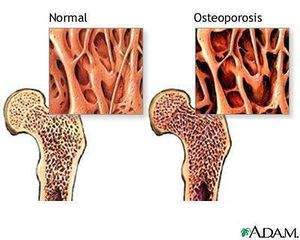

Osteoporosis

La osteoporosis es el término general para definir la porosidad del esqueleto causada por una reducción de la densidad ósea. En esta enfermedad se muestra la disminución de la resistencia del hueso, debido a una alteración en la remodelación ósea, por ello hay un descenso de la masa ósea, además de presentarse conductos amplios de reabsorción; en tanto que la concentración de calcio en la matriz es normal.

La osteoporosis secundaria es la más frecuente y asociada con la tercera edad, la menopausia y la actividad física reducida.

En homeostasis la unión del estrógeno con los osteoblastos a través de receptores específicos, estimula a los osteoblastos para producir y secretar matriz ósea. Con el decremento de la secreción de estrógeno por la menopausia, la actividad osteoclástica (reabsorción) se vuelve mayor q la osteoblástica (formación de tejido óseo nuevo), teniendo como consecuencia la reducción de la masa ósea, volviendo frágil al hueso, por incapacidad para el soporte de las fuerzas de tensión.